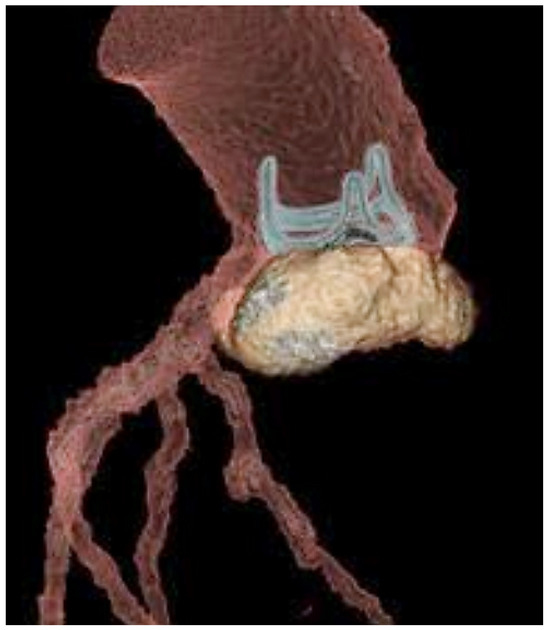

3. The Clinical Problem

4.1. Enterococcal Pili and Infective Endocarditis

4.2. Lesion Development and Progression of Infective Endocarditis in Heart Structure